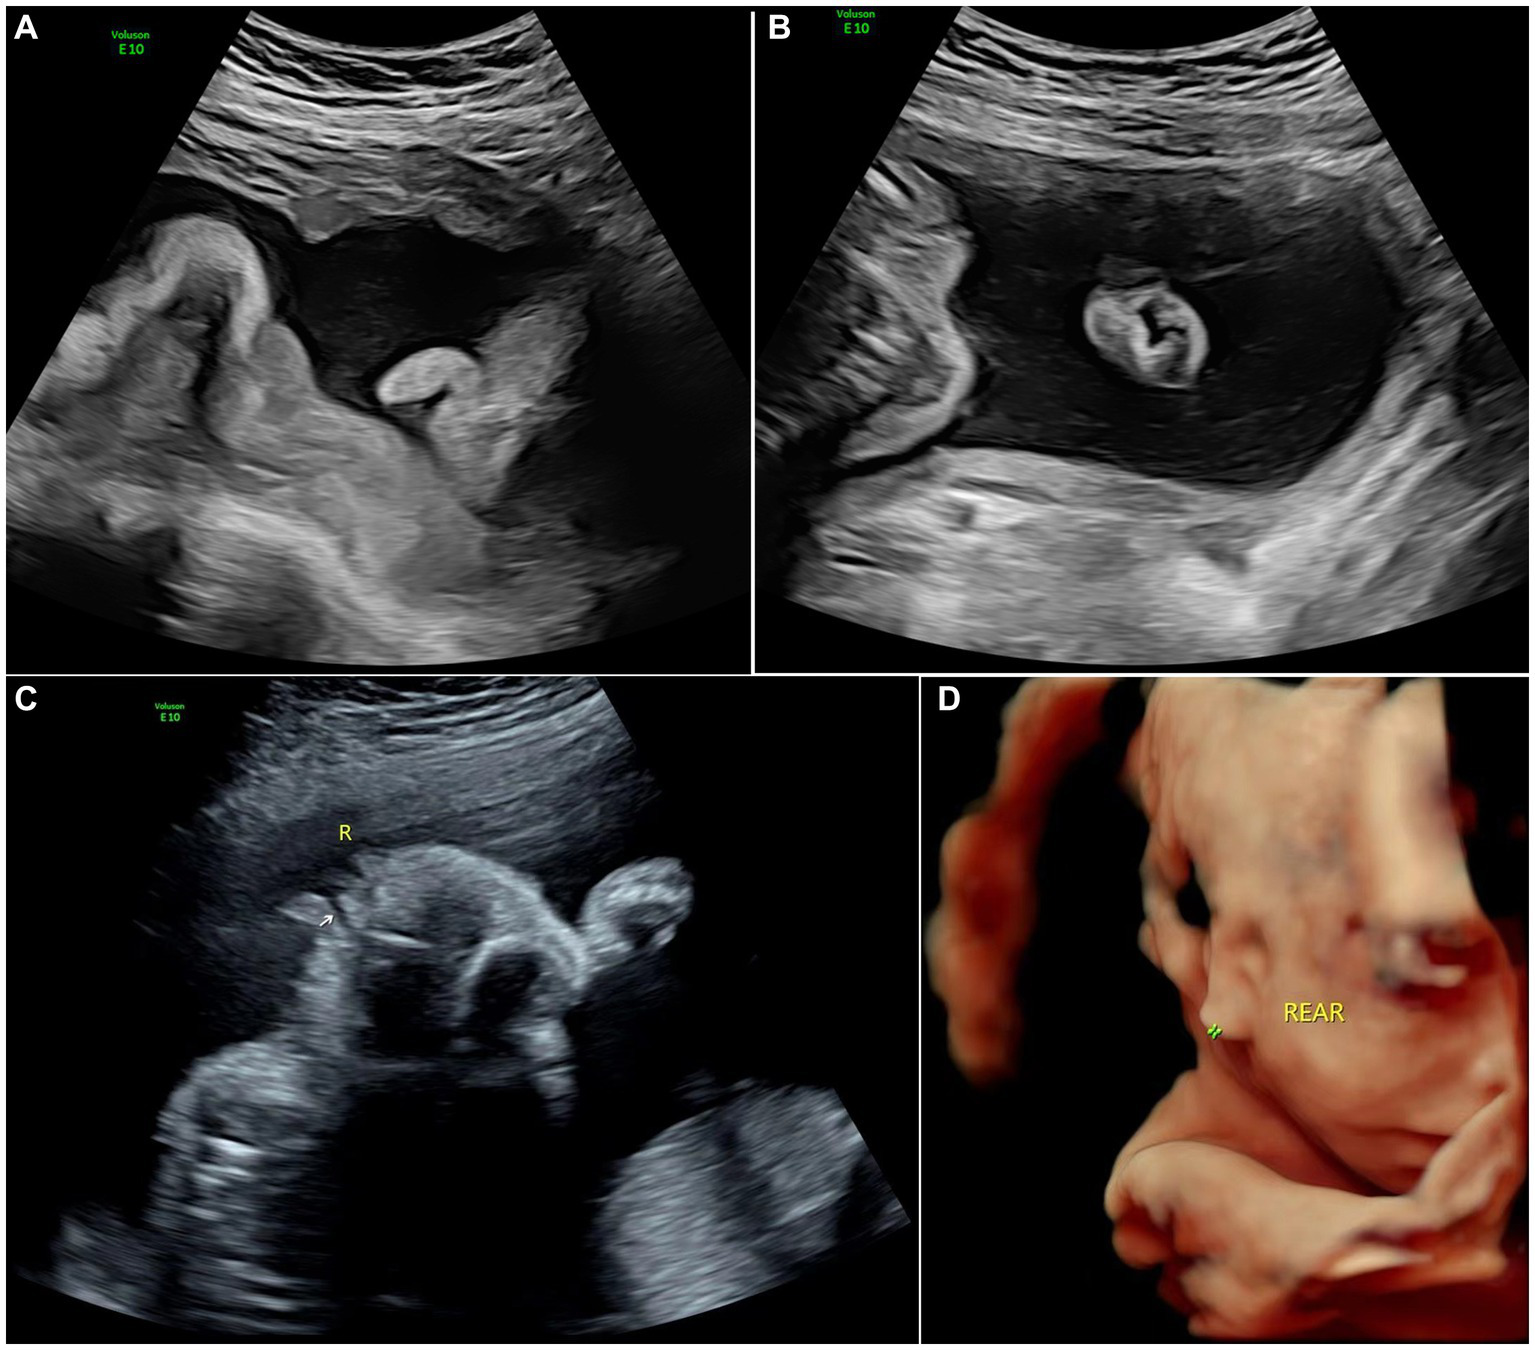

As indicated in research literature on the standard for the normal diameter of the fetal auricle, an external auricle length less than twice the standard deviation of the mean fetal auricle length at the same gestational age indicates microtia (1). In this study, all 81 cases met the diagnostic criteria for microtia and were accompanied by varying degrees of morphological abnormalities. Microtia can be morphologically classified into 4 types from mild to severe: type I: mild deformity and a slightly small auricle with a clear structure; type II: moderate deformity and a small auricle with a partially preserved structure (Figure 2); type III: severe deformity with only partial auricular cartilage and earlobe preserved, accompanied by atresia of external acoustic meatus (Figure 3); and type IV: anotia with atresia of the external acoustic meatus.

Figure 3

Images of type III of microtia: (A) 2D sonography and (B) photo (induced labor) of microtia type III accompanied by an accessory auricle; (C) 2D sonography of unilateral microtia type III accompanied by atresia of external acoustic meatus; and (D) 3D sonography of Unilateral microtia type III.